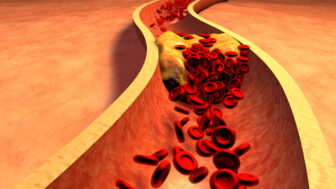

Vysoký obsah flavanolov v zelenom čaji výrazne pomáha znižovať hladinu „zlého“ cholesterolu (LDL), čím podporuje zdravie srdca a ciev. Nie je náhodou, že práve obyvatelia Okinawy v Japonsku, ktorí tento čaj pijú každý deň, patria medzi najdlhšie žijúcich ľudí sveta.

Pravidelné pitie malého množstva červeného vína (ideálne jeden pohár denne) preukázateľne znižuje riziko kardiovaskulárnych ochorení, cukrovky 2. typu a niektorých typov rakoviny. Je však dôležité dodržiavať odporúčané množstvá, pretože nadmerná konzumácia alkoholu naopak zdravie poškodzuje.

Prírodná brusnicová šťava, najlepšie bez pridania cukru, je bohatým zdrojom polyfenolov a antioxidantov. Tie pôsobia protizápalovo, znižujú riziko vzniku srdcových ochorení a pomáhajú udržať zdravie močových ciest.

Vďaka obsahu vitamínov C, B6 a E podporuje brusnicová šťava celkovú vitalitu a obranyschopnosť organizmu. Ak ju budete pravidelne popíjať, nielenže si predĺžite život, ale zároveň urobíte aj niečo prospešné pre svoje srdce a celkové zdravie.